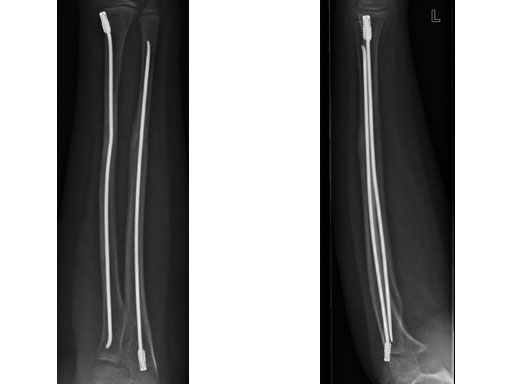

Elastic stable intramedullary nailing (ESIN) has become the method of choice for internal fixation of femoral and tibial shaft fractures in children of 4-14 years of age. In the lower extremity, ESIN treatment may be complicated by loss of reduction following push-out of the nails at the entry site, especially in unstable femoral shaft fractures. The rate of this complication nail migration with subsequent soft-tissue and skin irritation was reported to be as high as 5-12% until end caps (which lock the nails at the entry point) became available. The use of end caps avoids postoperative instability, even in heavier, older patients with unstable fracture types. To maximize stability of ESIN-instrumented unstable fractures, end caps require properly placed nails that are correctly bent. It is essential to cut the nails to a correct length at the entry site to ensure adequate anchoring of the nails in the caps and anchoring of the cap in the cortical bone respectively. The end caps are equipped with a self-cutting device and are put over the cut ends of the nails like a hollow screw that is fixed in the cortical bone at the nail entry site. A special bevelled impactor is mandatory for the final nail positioning. The position of the nail inside the end cap can easily be visualized since the caps are semi-radiolucent. The end caps also protect the soft tissues from the cut nail ends, and improve retrieval because the cap facilitates nail placement and creates a space around the nail ends for the extraction pliers. Only one small, extra instrument, the driver for the caps, is required.

Following the positive experiences with the end caps, there is also a need for small end caps. On the one hand there has been a request for a safer and more comfortable stabilization of clavicle fractures, on the other hand there has been a request for a safer stabilization of problematic forearm fractures in older children.

Biomechanical studies performed by the AO Foundation show that end caps increase the push-out force six times over that of conventionally inserted nails. A clinical study run by the Department of Pediatric Surgery in Bern demonstrated the clinical efficacy.